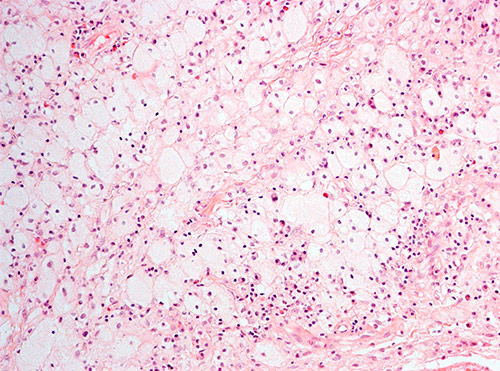

Histologisk undersøkelse hadde vist inflammatorisk prosess med mange makrofager, spredtliggende og enkelte grupper av lymfoide celler, spredte plasmaceller, nøytrofile og eosinofile granulocytter (fig 1). Atypiske celler, granulomatøs betennelse eller vaskulitt var ikke påvist. Spesialfarging for sopp, bakterier og mykobakterier var negativ. Ved rutinemessig immunhistokjemisk undersøkelse var makrofagene positive for CD68. De små lymfoide cellene var B-celler positive for CD20 samt T-celler positive for CD4 og CD8.

Ved ny gransking ble det poengtert at makrofagene hadde rikelig med lyst skummende cytoplasma, forenlig med skummakrofager. Immunfenotyping viste at de CD68-positive makrofagene var negative for CD1a og S100. Patolog konkluderte med at det morfologiske bildet passet med Erdheim-Chesters sykdom.

Ved immunhistokjemiske undersøkelser finner man ved Erdheim-Chesters sykdom CD68-positive og CD1a-negative histiocytter, mens man ved langerhanscellehistiocytose påviser CD1a-positive histiocytter. I de fleste tilfellene av Erdheim-Chesters sykdom (80  %) er farging for S100-protein negativ. Diagnosen Erdheim-Chesters sykdom settes ut fra en kombinasjon av kliniske, bildediagnostiske og histologiske funn.